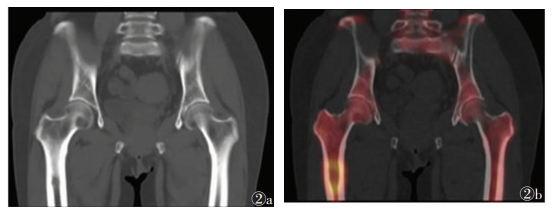

2 结果49例共91处疼痛部位,发生于颅骨颈椎(图 1)、肋骨、髋关节(图 2)、骶髂关节(图 3)、胸椎(图 4)等处的疼痛较剧烈且为持续性疼痛,夜间更明显,并随时间推移逐渐加重,常规非甾体药物缓解不明显。SPECT/CT融合断层显像示阳性40处,其中真阳性35处,假阳性5处;阴性51处,其中真阴性49处,假阴性2处。SPECT/CT融合断层显像对肿瘤疼痛骨转移瘤诊断的敏感度为94.6%(35/37)、特异度为90.7%(49/54)、准确率为92.3%(84/91)。后经病理及临床随访证实5处假阳性病灶中3处为退行性病变,由于存在隐匿性骨质破坏导致骨代谢增高,核素浓聚;余2处,1处为髓腔炎症所致,1处为原发骨肿瘤。2处假阴性病灶由于病灶体积较小,1处位于胸椎重叠部位,1处示溶骨性改变,最后融合显像显示放射性浓聚不明显而导致漏诊。

| 图 2 女,55岁,右侧乳腺癌术后1年6个月,股骨及髂骨2处疼痛 图 2a 骨盆CT平扫示:两侧髂骨、双侧髋臼、右侧股骨头、右侧股骨上段多发溶骨性骨质破坏区,皮质溶解 图 2b SPECT/CT局部融合显像示:两侧髂骨、骶椎、髋臼、右侧股骨头、右侧股骨上端多发散在斑片状放射性核素聚集灶,部分呈“冷区”改变 |